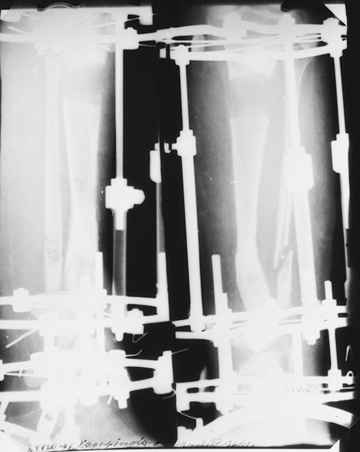

На первом этапе аппаратом Илизарова закрыто устранена деформация голени.

На втором этапе произведёно освежение краёв костных фрагментов б/б и м/б костей с приданием проксимальному фрагменту б/б кости впалой, а дистальному выпуклой формы, открытие канала проксимального фрагмента и погружной остеосинтез, а также остеотомия б/б кости в в/3 и м/б кости на границе с/3 и н/3 голени. Больной проводился одновременный бифокальный компрессионно-дистракционный остеосинтез. Достигнуто 11 см. удлинение и сращение ВПГ.

Срок лечения 11 месяцев. Наблюдение 2 года.